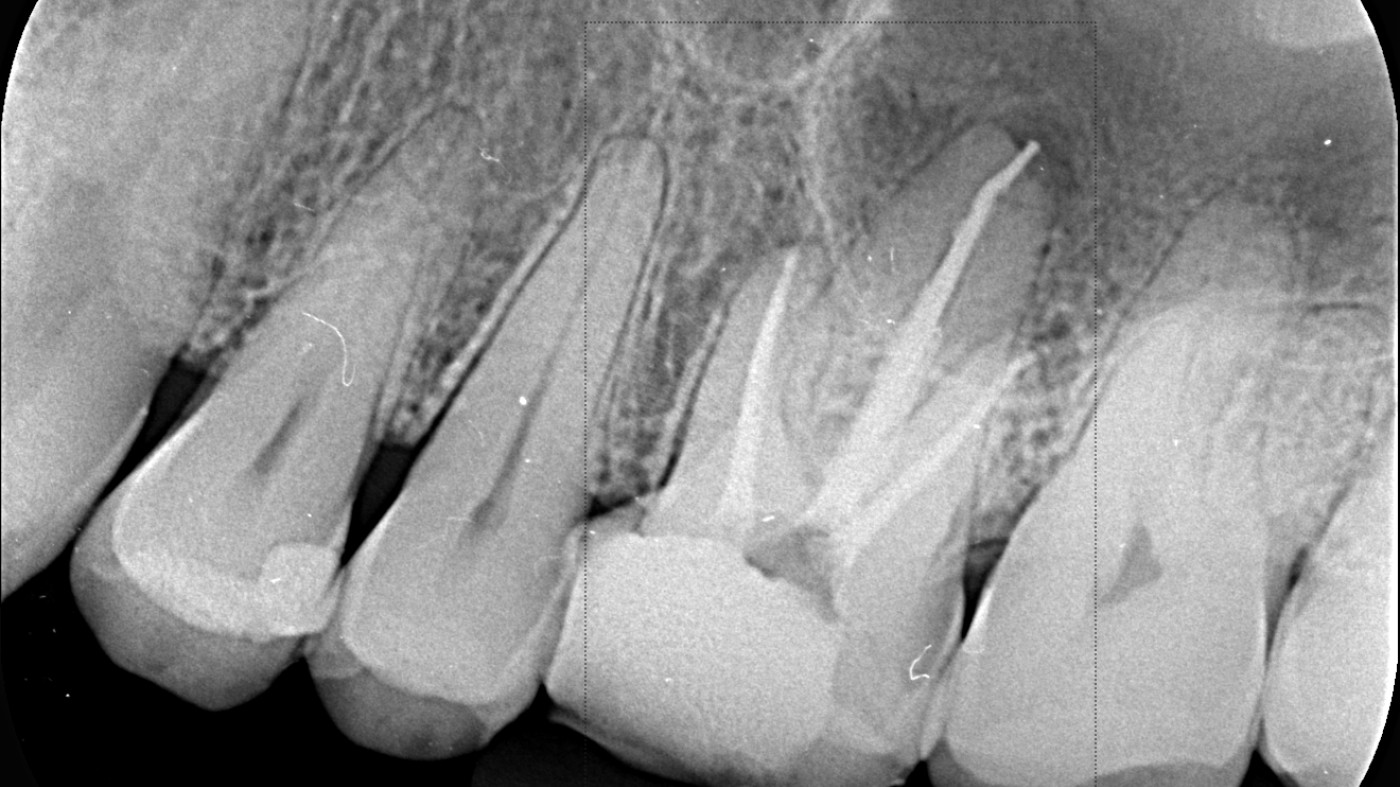

Podczas tego praktycznego wydarzenia wspólnie odkryjemy, jak zaawansowane technologie obrazowania rewolucjonizują współcześnie diagnostykę. Razem zgłębimy strategie efektywnego wykorzystania różnych technik diagnostycznych, takich jak tomografia komputerowa i zdjęcia rentgenowskie, w celu precyzyjnej oceny stanu tkanek zęba oraz korzeni. Dokonamy także analizy obrazów i pokażemy, jak dokładne diagnozy mogą wpłynąć na skuteczność leczenia endodontycznego.

• diagnostyką anatomii zębów kwalifikowanych do leczenia endodontycznego,

• możliwościami lokalizacji złamań, pęknięć oraz perforacji w badaniach obrazowych,

• diagnostyką zmian OKW,

• prawidłowym dokonywaniem pomiarów w obrębie badań CBCT,

• odpowiednim zlecaniem/wykonania badań CBCT przydatnych w endodoncji,